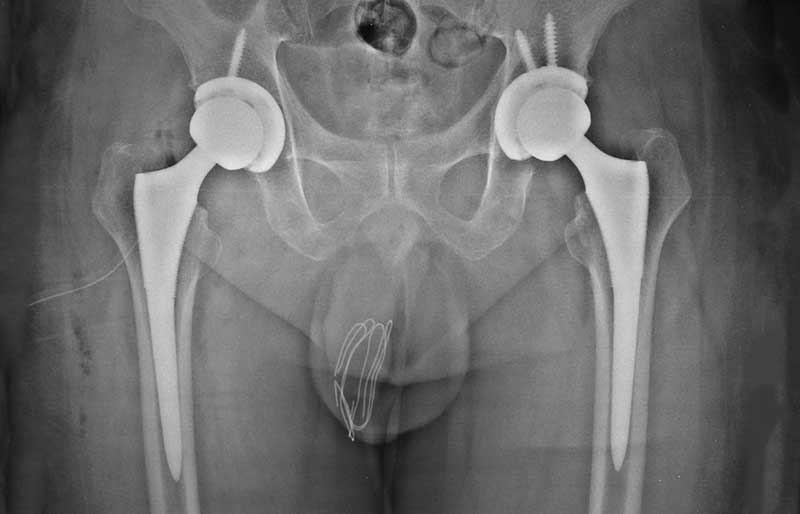

Operasi penggantian sendi panggul merupakan pengobatan terbaik untuk osteoartritis panggul stadium yang berat. Ada empat tujuan operasi ini, yaitu menghilangkan rasa sakit sendi yang telah rusak, memperbaiki lingkup gerak sendi yang sebelumnya kaku dan terbatas, mengembalikan kemampuan penderita melakukan aktivitas harian tanpa rasa sakit, dan meningkatkan kualitas hidup sehingga penderita kerusakan sendi dapat menjalani hidup secara aktif bebas dari nyeri sendi panggul.

Operasi penggantian sendi panggul biasanya berlangsung sekitar 1,5 sampai 2 jam. Sama seperti operasi yang lain, di jaman modern ini operasi penggantian sendi panggul merupakan operasi yang aman bagi orang tua (pada kenyataannya, sebagian besar penderita osteoartritis sendi panggul adalah para orang tua). Dengan kemajuan teknologi dan ilmu kedokteran modern, operasi penggantian sendi panggul aman bagi orang tua yang biasanya juga menderita kencing manis, penyakit jantung dan tekanan darah tinggi.